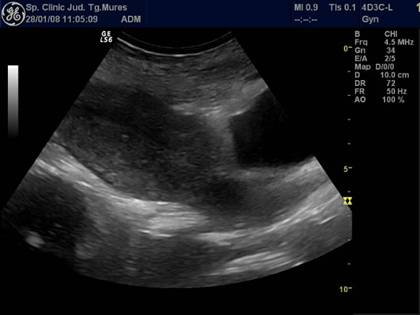

Fig. Nr.333. Lauzie ziua a XII a postoperatie cezariana